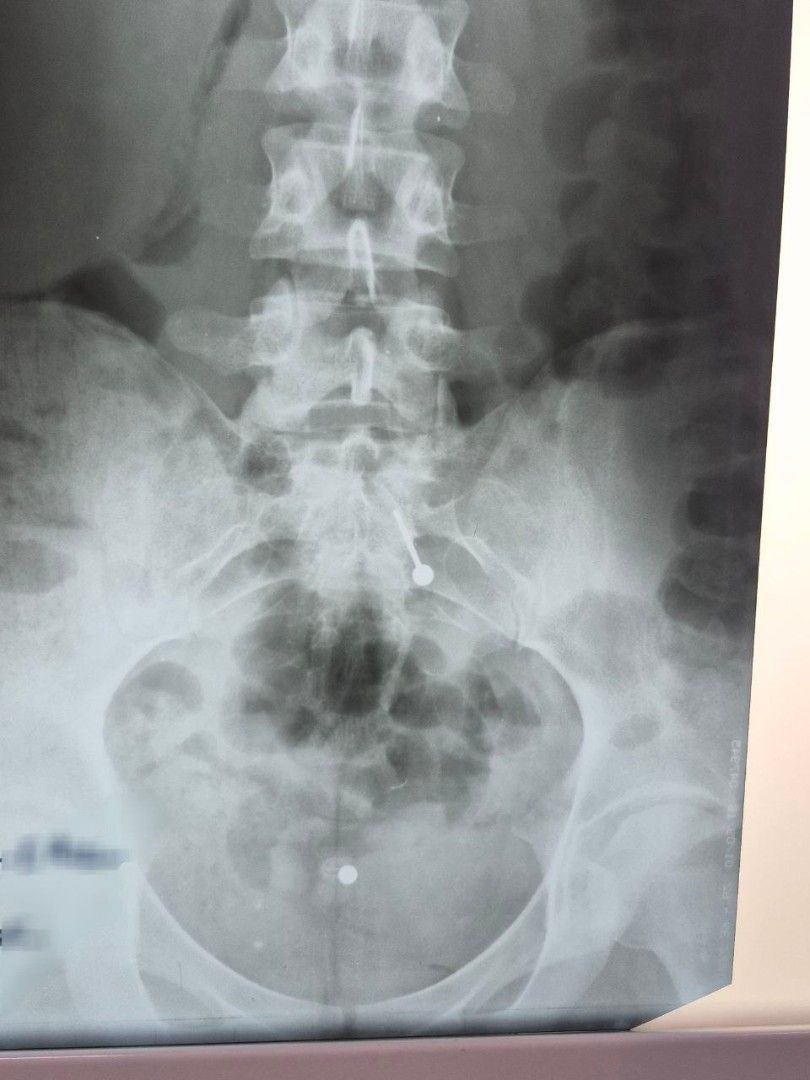

В Балаковскую горбольницу обратилась 20-летняя девушка. Она случайно проглотила украшение для пирсинга языка — металлическую «штангу» с шариком во время еды.

К врачам девушка обратилась не сразу. К тому времени инородный предмет уже переместился в тонкий кишечник, и безопасно извлечь его с помощью эндоскопа стало невозможно. Теперь, вероятно, пирсингу придётся выходить «естественным» путём.